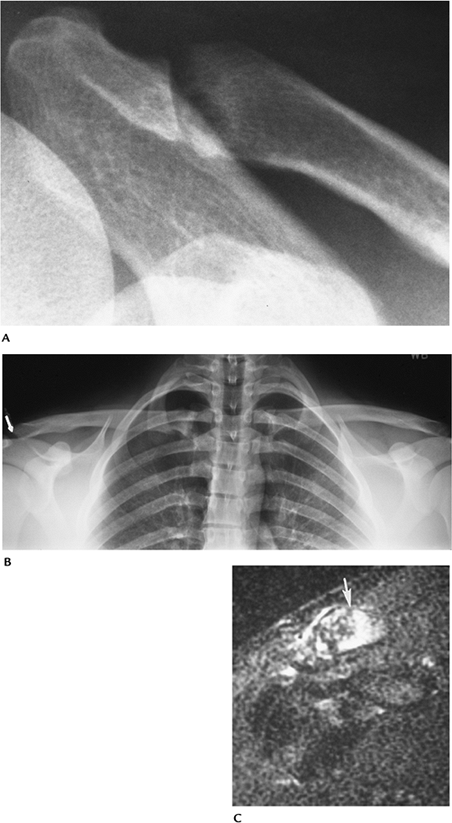

FIGURE 7-9 (A) AP radiograph of a minimally displaced fracture of the mid-clavicle (arrow). (B) AP tomogram of a medial clavicular fracture. (C) AP radiograph of a distal clavicular fracture with coracoclavicular ligament disruption (double arrow).